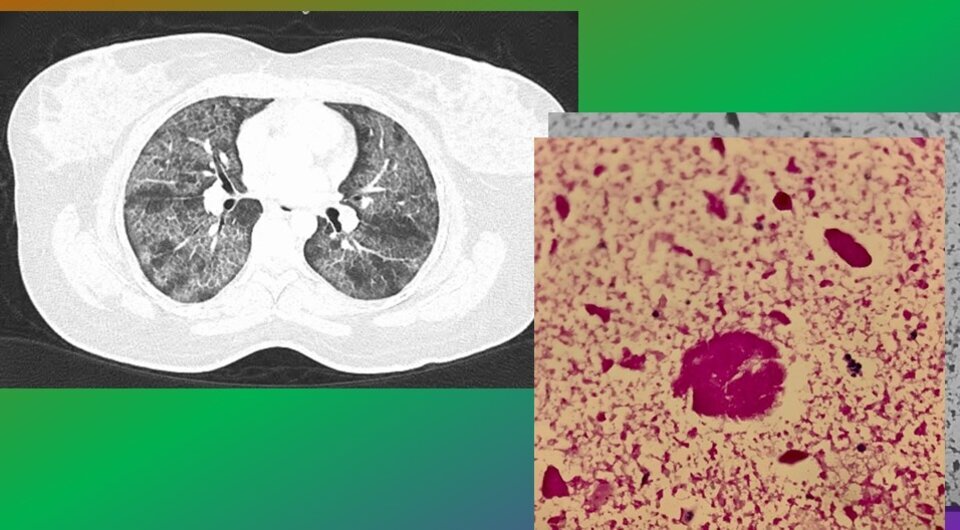

Cara Louise Weldrick et al. / BMJ Case Reports, 2023

Рентгенография грудной клетки показала обширные двусторонние инфильтраты в нижних долях легких. Компьютерная томография грудной клетки выявила диффузные двусторонние затемнения по типу «матового стекла» с утолщением междолевой плевры. Жидкость из бронхоальвеолярного лаважа имела характерный молочный оттенок, и в ней не обнаружили патогенных микроорганизмов. Трансбронхиальная биопсия и цитологическое исследование жидкости бронхоальвеолярного лаважа показали обилие гранулированного и уплотненного белкового материала. Врачи провели дополнительное исследование и обнаружили антитела к ГМ-КСФ, что дало основание для диагноза легочного альвеолярного протеиноза.